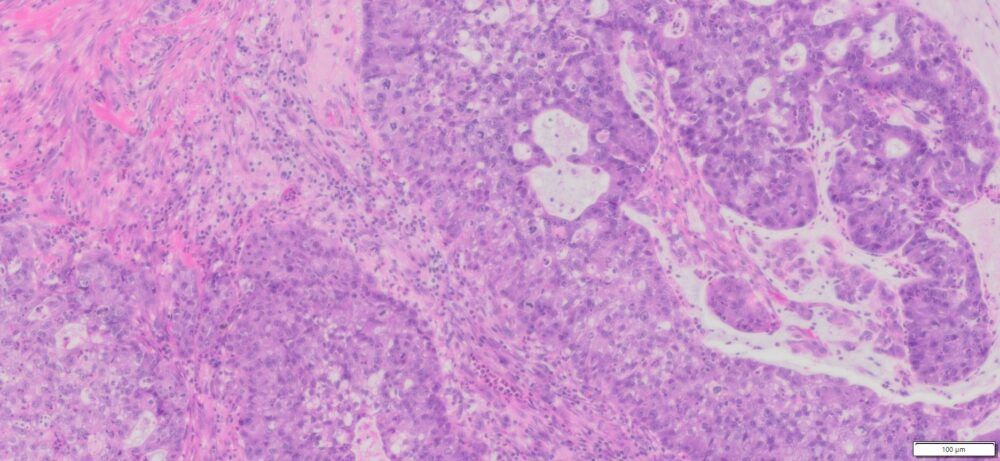

Description

| Organ& Tissue | Pathology Diagnosis | Gender/Age | % Tumor Area | Grade | TMN Stage | Biomarkers |

| Human Cervix | Cervical Adenocarcinoma with mucinous differenciation | Female/38 | 82% | II | NA | P16(+),P40(-),CK5(+), PD-L1 (+) |